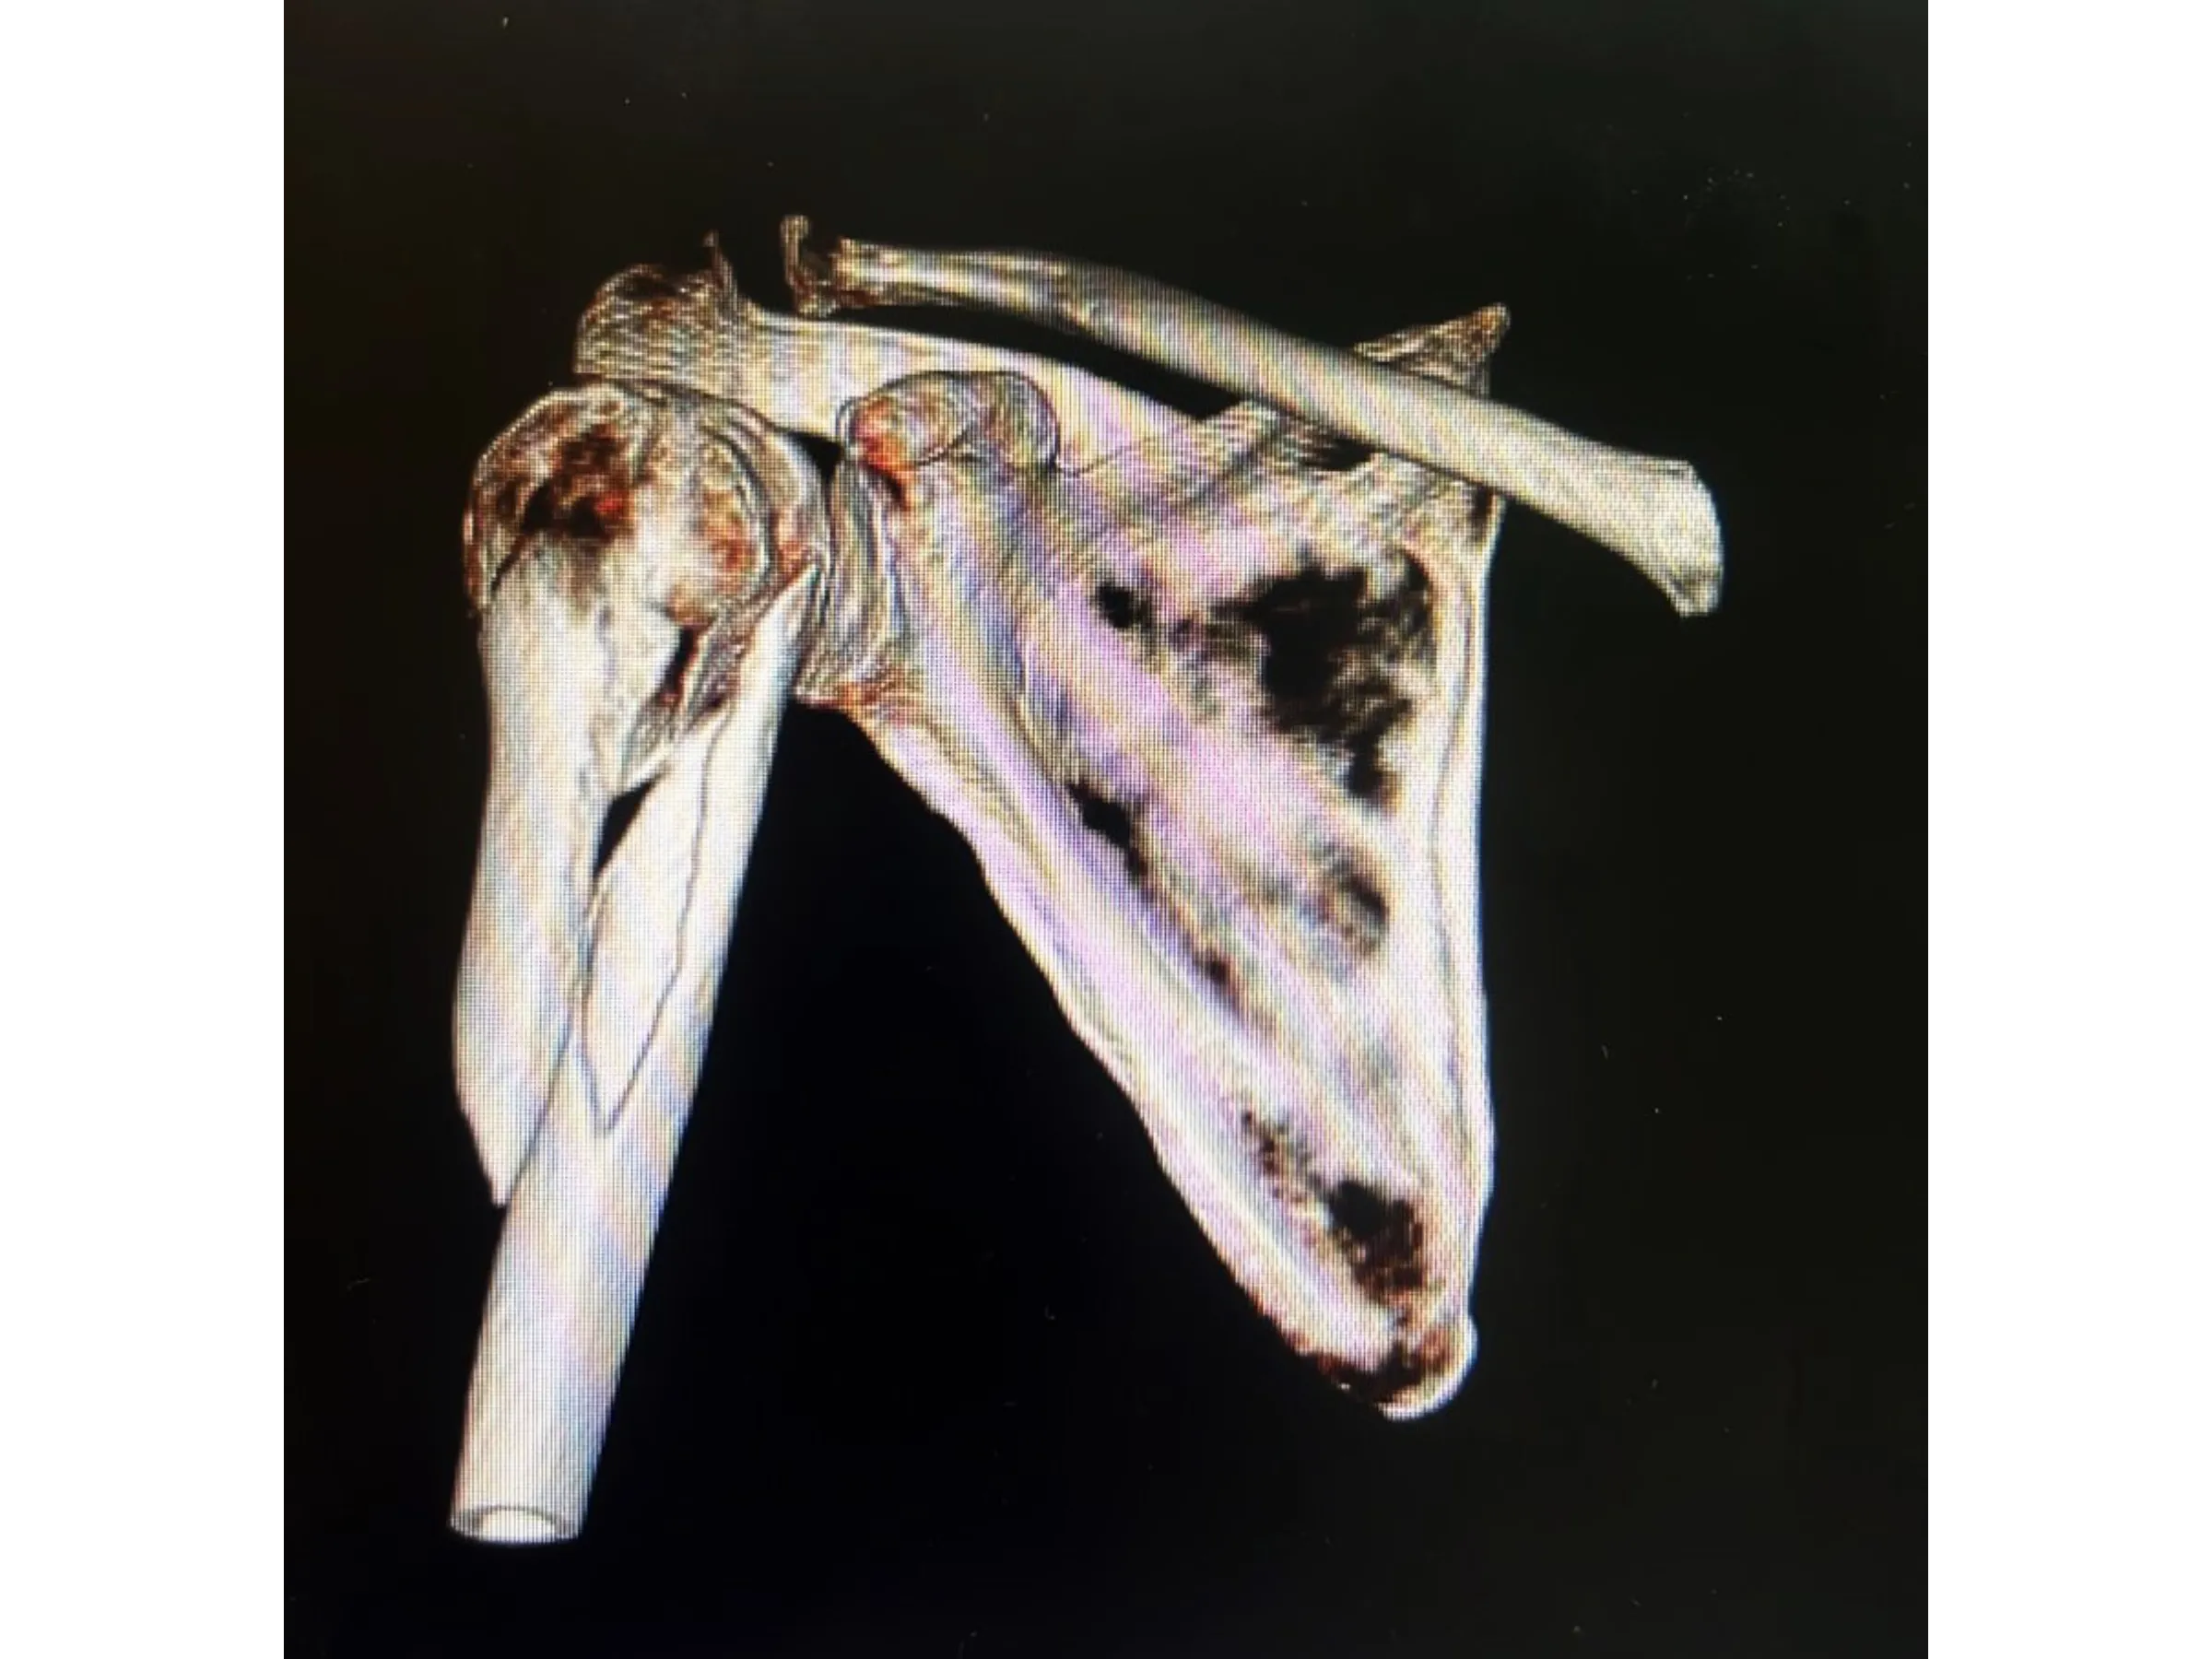

Proximal humerus fractures in elderly patients require effective stabilization with minimal tissue damage. This training presents a fluoroscopy-guided surgical approach using a long intramedullary nail that preserves the rotator cuff and ensures secure fixation. The technique is demonstrated step-by-step from a surgical perspective, focusing on anatomical and biomechanical precision.

- Muscle dissection and rotator cuff preservation.

- Muscle and Tendon Preservation: Respectful dissection of the deltoid fibers and controlled rotator cuff tenotomy.

- Stable Intramedullary Fixation: Insertion of a long rod with multiple locking screws, including metaphyseal screws.